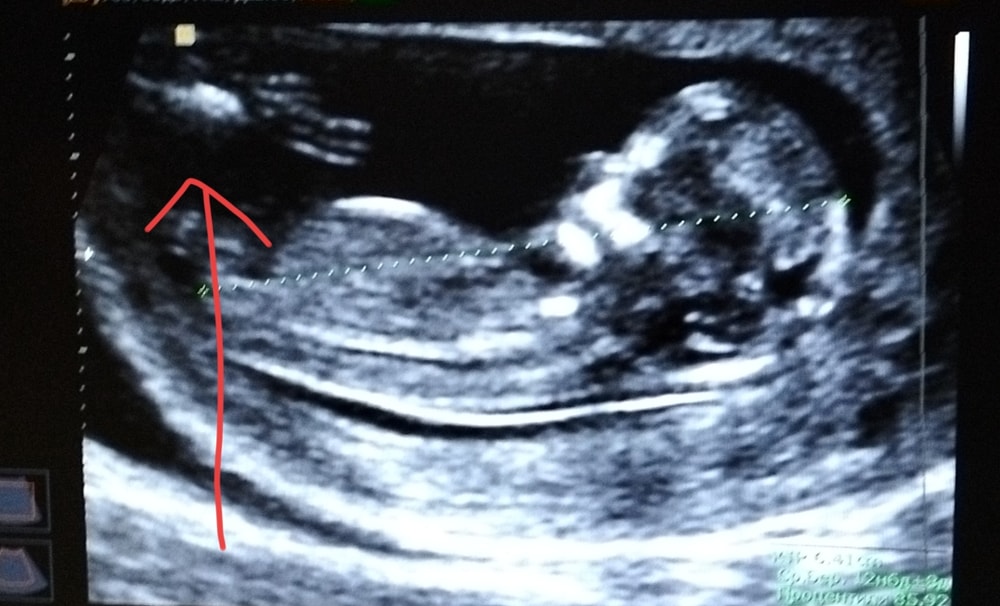

Что за рука на УЗИ?

С чего вы взяли, что это рука? 😂 просто ваши ткани. Без опыта работы на аппарате узи можно там найти хоть клоуна с шариками, к тому же по фото)

😀ну на руку похоже, но рука какая-то очень большая для второго плода(если вы об этом), это артефакт просто))

УЗИ - это звуковая волна, а не фото. Она (волна) не может передать изображение в высокой четкости. Ребенок подвинулся + подвинули датчик и вот изображение исказилось на снимке. Если врач ничего не сказал, то можете не переживать, все у ребенка хорошо и на своих местах